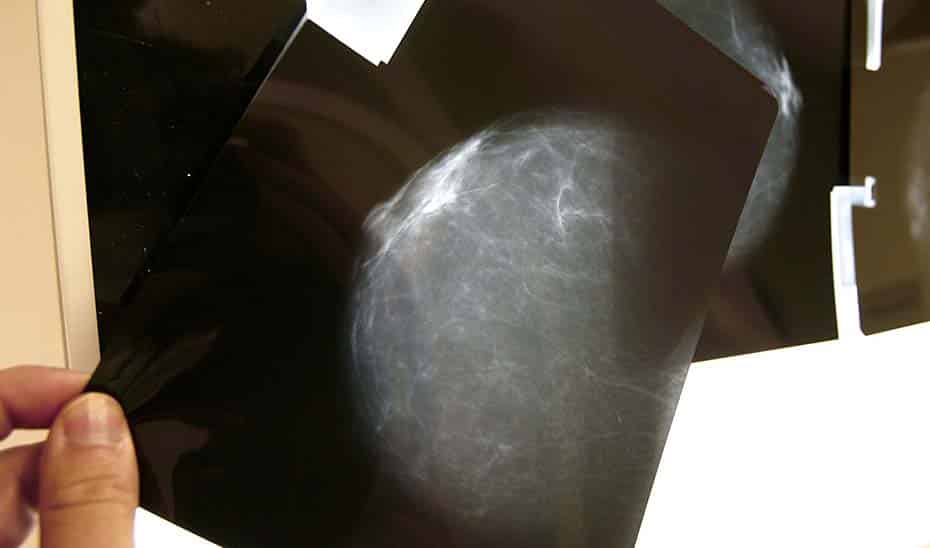

El Servicio Andaluz de Salud (SAS) ha iniciado un proceso de comunicación directa con aproximadamente 2.000 mujeres cuyos resultados en el programa de cribado de cáncer de mama no fueron concluyentes. Estas pacientes presentaban lesiones dudosas que, aunque no se consideran graves, requieren un seguimiento médico fuera del programa regular de cribado.

El programa, en funcionamiento desde 1995, ha experimentado un crecimiento sostenido y se encuentra en un ciclo de mejora continua. El aumento en el número de mamógrafos ha permitido gestionar más citas y realizar más mamografías, con la participación rondando el 70-75% y la cobertura cerca del 80% para mujeres de 49 a 71 años. Cada año, se detecta la sospecha radiológica de cáncer de mama en unas 2.100 mujeres.